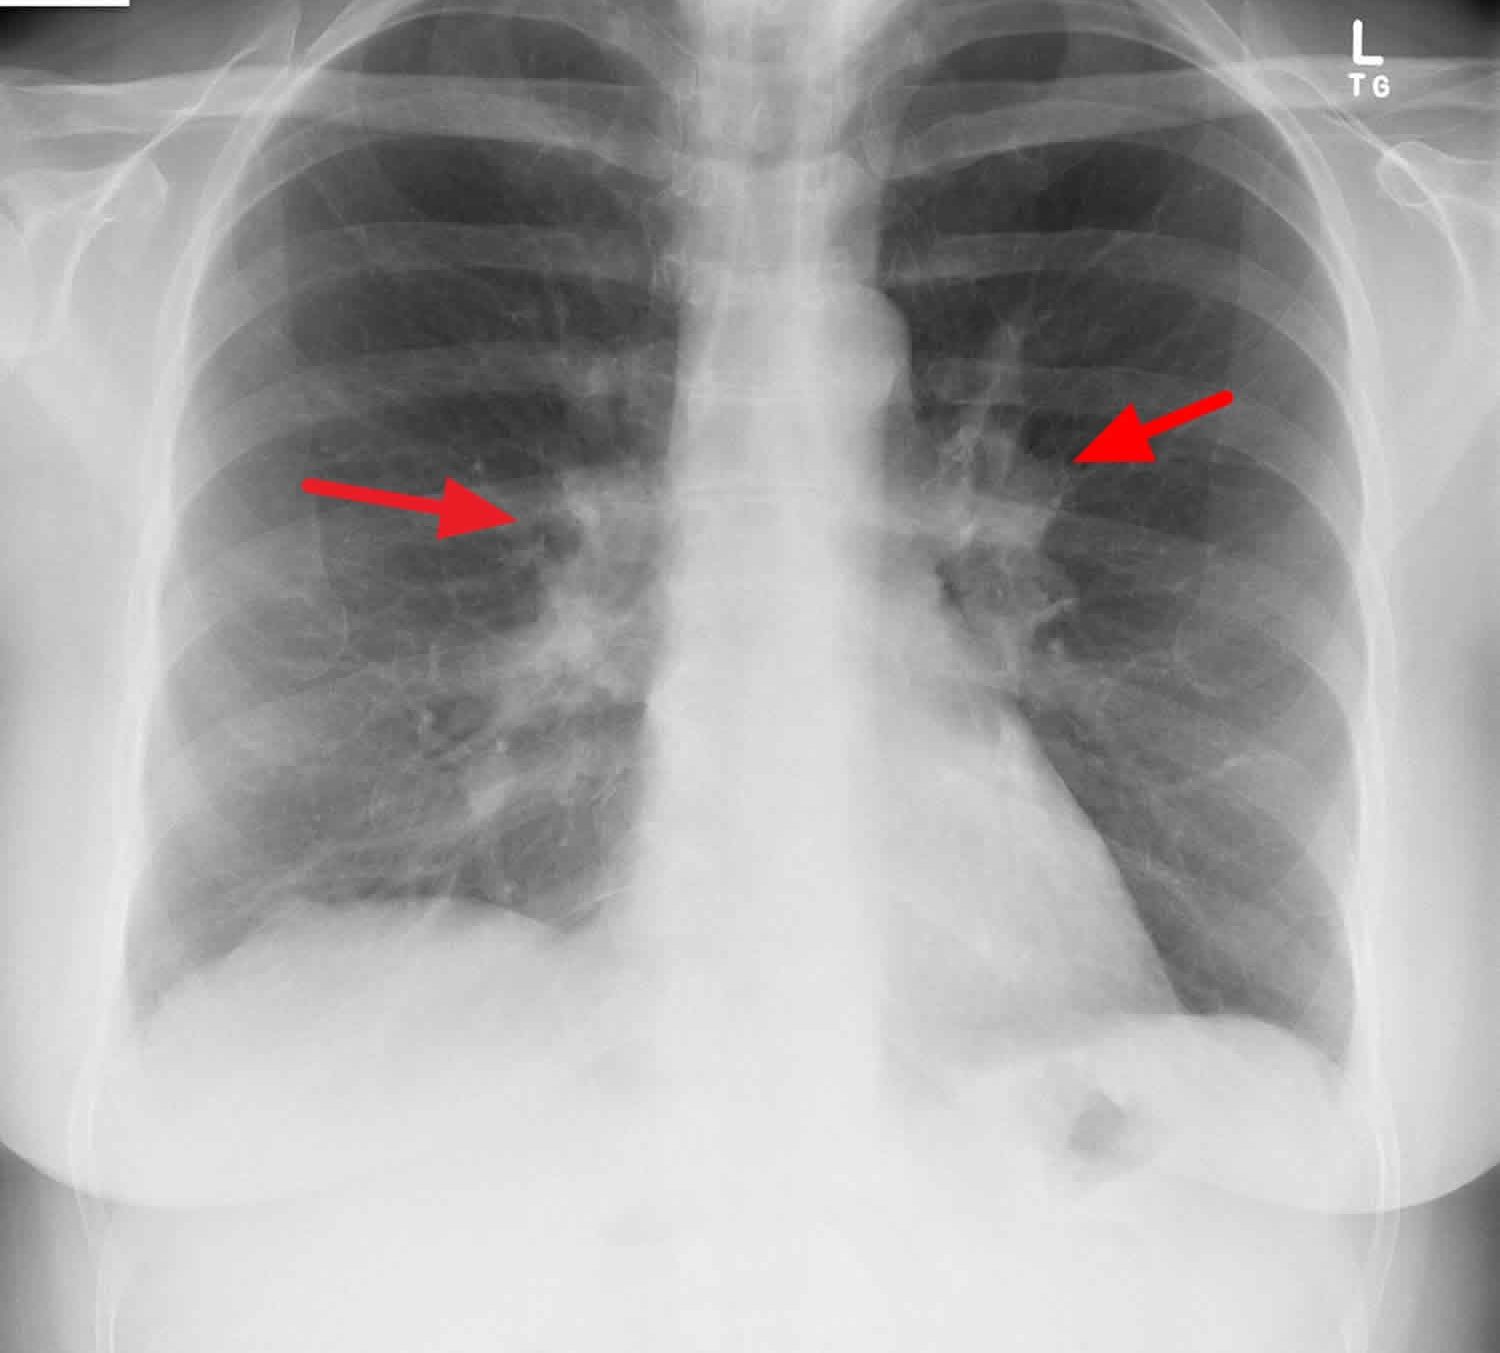

The enlargement of the right hilar lymph nodes is hilar adenopathy. Various factors are responsible for the expansion of the right hilar lymph node or hilar adenopathy in particular. Now, what are those factors or causes?

It may be caused; by infections such as mycoplasma, tuberculosis, histoplasmosis, and coccidioidomycosis. It may also be caused; by heart failure and sarcoidosis. Other causes include; inorganic dust diseases such as silicosis and berylliosis. It may be due to the result of malignancy, that is, carcinoma or lymphoma. Few individuals also report developing enlargement of this lymph node due to the consumption of drugs.

In unexplained conditions, imaging studies, tissue biopsy, and laboratory tests are recommended in identifying if any enlarged hilar lymph node is visible or not. However, imaging can easily recognize the distribution and size of the lymph node way more accurately than any examination method. Ultrasound is a non-invasive method to assess these nodes.